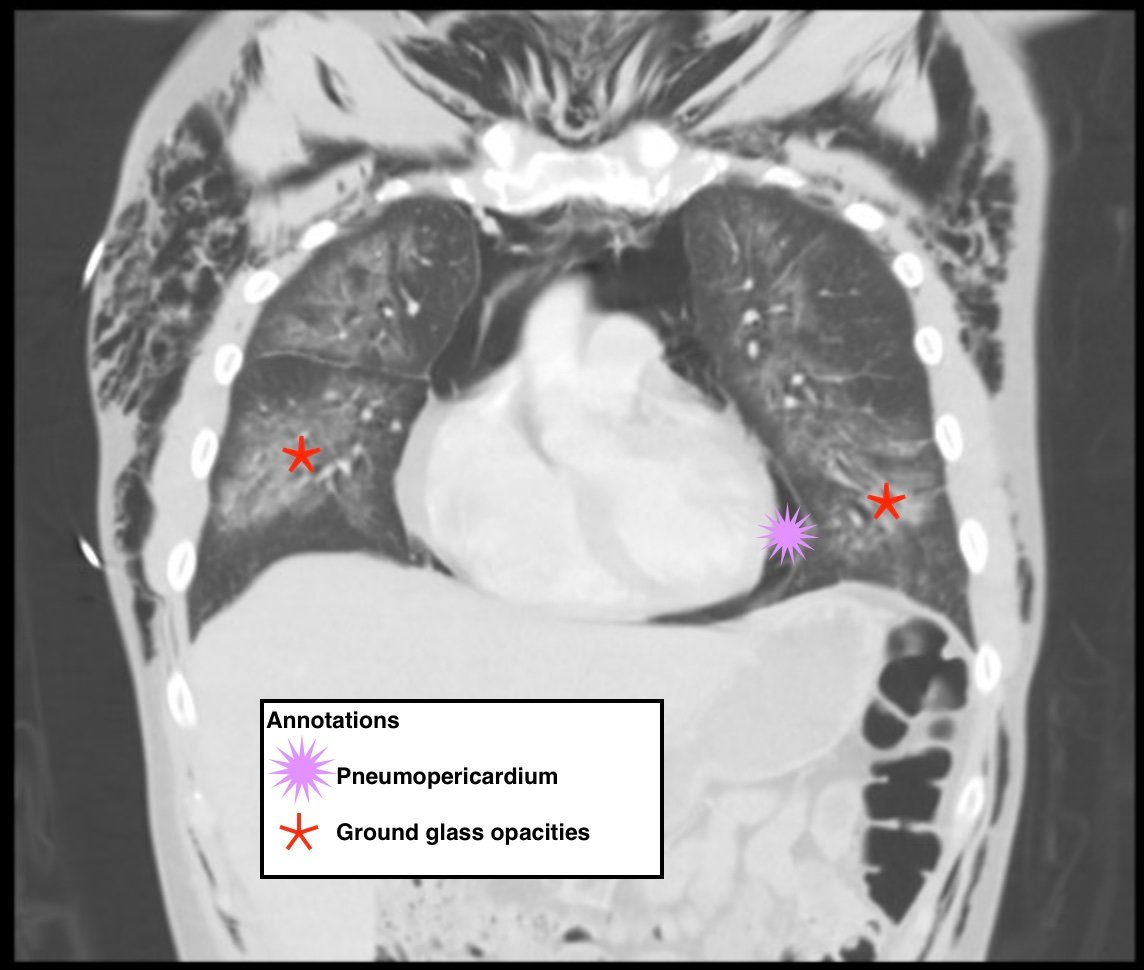

Electronic cigarette (e-cigarette) or vaping associated lung injury (EVALI) cases have increased with the popularity of e-cigarettes in the mostly young, healthy population. Some common symptoms associated with EVALI include shortness of breath and chest pain, and the most common diagnostic imaging findings are organizing pneumonia and diffuse alveolar damage seen on computed tomography (CT). Pneumomediastinum is a known sequela of EVALI.1 In the setting of pneumomediastinum in EVALI, EVALI is a diagnosis of exclusion, so other sources of pneumomediastinum need to be evaluated. EVALI has diverse presentations, and this case is a unique representation of a disease process that is becoming more commonplace with the increase in popularity of vaping. It is important to be aware of the clinical symptoms of EVALI, which can be nonspecific and can include gastrointestinal symptoms along with respiratory symptoms. It is equally important to recognize the diverse image findings of EVALI, which can include subcutaneous emphysema and pneumomediastinum. In this case, pneumomediastinum is seen in EVALI, and the patient was successfully treated with empiric antibiotic coverage, steroids, and conservative measures—making sure to limit any coughing or increases in intrathoracic pressure that can cause worsening of pneumomediastinum.

EVALI, vaping, pneumomediastinum, E-cigarette, ground-glass opacity.